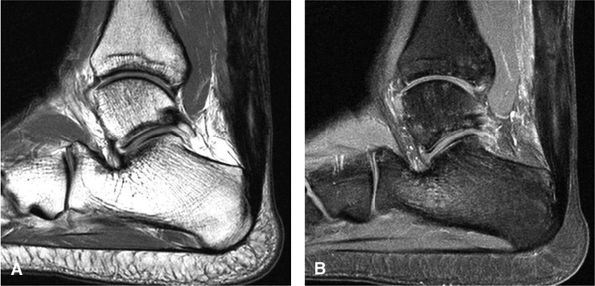

FIGURE 5.130 ● Type 1 tibialis posterior tendon tear associated with a medial malleolus osseous spur. The normal tibialis posterior tendon is approximately twice the cross-sectional diameter of the flexor digitorum longus. In a type 1 tear the PTT may demonstrate increased thickening, with a cross-sectional diameter up to 5 to 10 times larger than the adjacent flexor digitorum longus tendon. (A) Lateral graphic with an axial insert. (B) Axial FS PD FSE image.

Type 1: There is tendon hypertrophy with heterogeneous signal intensity in intrasubstance vertical splits (Fig. 5.130). Associated findings include increased signal intensity (intrasubstance striations) and girth at the distal tendon insertion to the navicular (a normal variant), osseous spurring with or without fatty marrow signal in the posteromedial aspect medial malleolus (see Fig. 5.130), and tendon dysfunction or dislocation with disruption of the flexor retinaculum (Fig. 5.131).

-